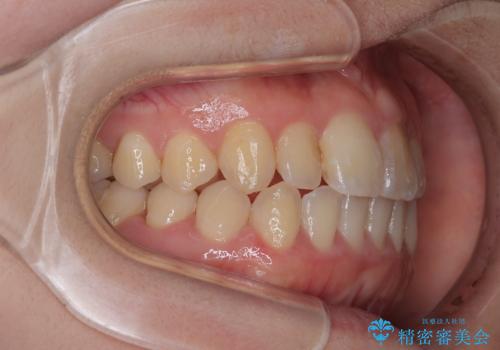

【インビザライン】前歯のがたつきを目立たない装置で治療

- 前歯の叢生を主訴に来院されました。目立たない装置を希望されたためインビザラインで治療を行いました。

IPRと拡大をし、叢生を治しました。右上2番は反対咬合でしたが短期間できれいに治りました。